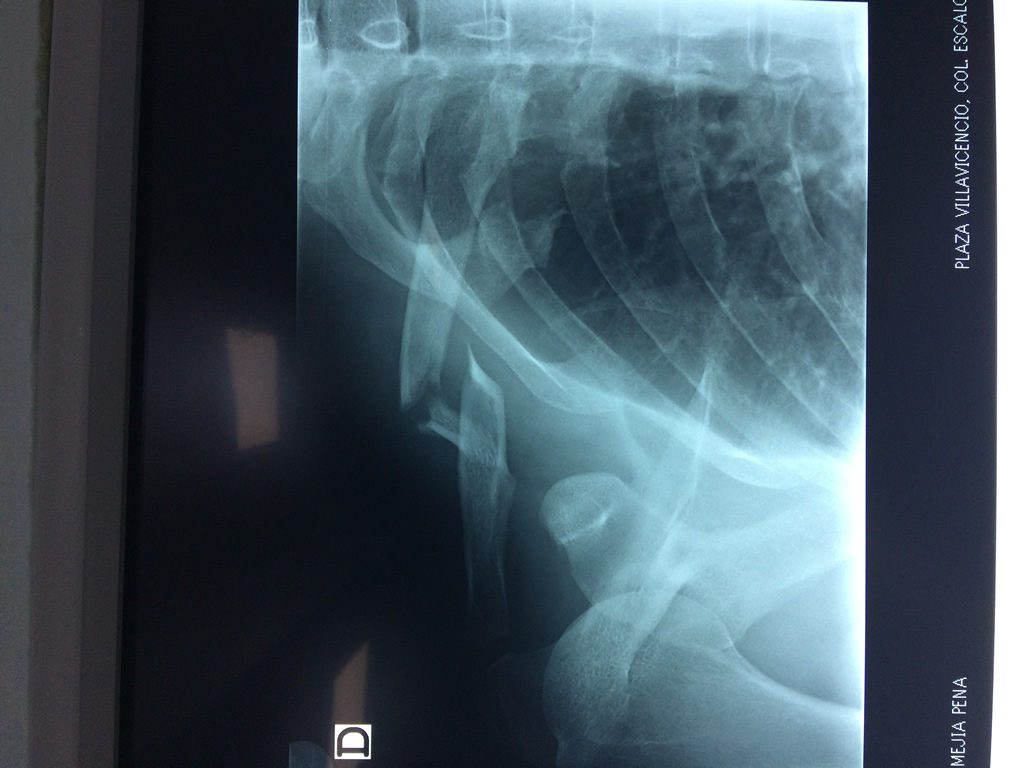

Cirugía de Fémur - Clavícula

La clavícula es un hueso largo, con forma de "S" itálica, situado en la parte anterosuperior del tórax. Junto con la escápula forman la cintura escapular. Se puede palpar por toda su longitud y se extiende del esternón al acromion de la escápula, siguiendo una dirección oblicua lateral y posterior.